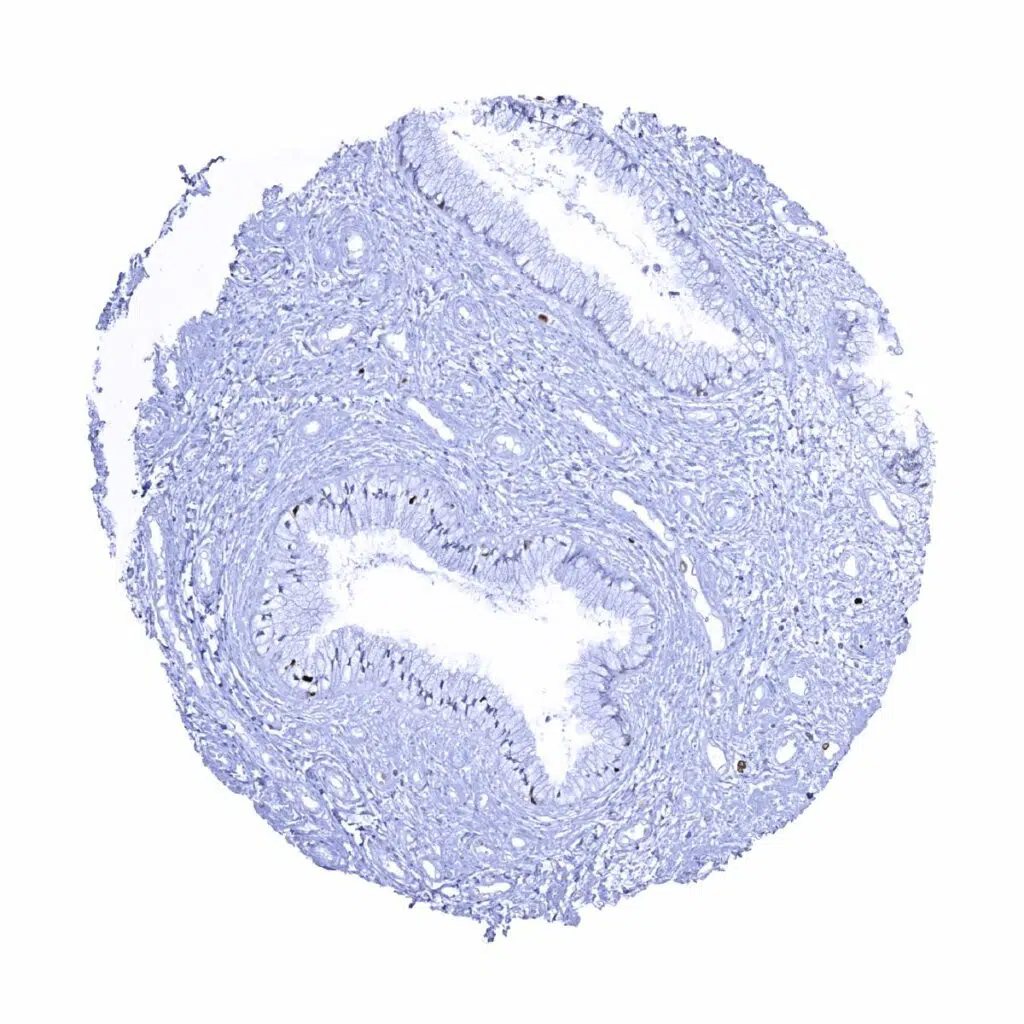

Appendix, mucosa – MCM7 immunostaining predominates in in epithelial cells of the crypts. Some lymphocytes are also positive